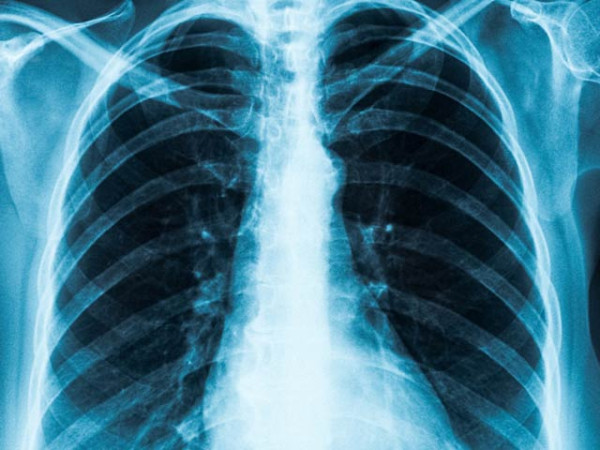

سینے کے ہزاروں ایکس رے کی بنا پر دل کے دورے کی شناخت کرنے والا کمپیوٹر پروگرام تیارکرلیا گیا ہے۔ فوٹو: فائل

ماہرین نے یہ سافٹ ویئر مصنوعی ذہانت کی بنا پر تیار کیا ہے۔ اس کا الگورتھم دل اور سینے کے ایسے ہزاروں ایکس رے کا ڈیٹا بیس پڑھ کر فیصلہ کرتا ہے جن پر انفرادی طور پر ڈاکٹروں نے اپنی رائے دی ہے اور اس کے مریض ہونے یا نہ ہونے کا اظہار کیا ہے۔ تاہم اس میں مصنوعی ذہانت ہی فیصلہ کن کردار ادا کرتی ہے بلکہ نہ صرف دل کے دورے بلکہ فالج کے خطرے سےبھی خبردار کرتی ہے۔

امریکا میں نیشنل انسٹی ٹیوٹ آف کینسر نے اس کی طبی آزمائشیں بھی کی ہیں۔ اس میں کل 11,430 مریضوں کے ایکسرے شامل تھے۔ مریضوں کی اکثریت دل کے دورے کے کنارے پر کھڑی تھی اور انہیں اسٹیٹن تھراپی سے گزارا گیا تھا۔ اس سے قلب کے متاثر ہونے کے خطرات کو ٹالا جاسکتا ہے۔

پھر ان تمام ایکسرے کا نئے مریضوں کے ایکس رے عکس سے موازنہ کیا گیا اور اسی بنیاد پر سافٹ ویئر نے دل کے دورے کے خطرے سے خبردار کیا۔ اس کے نتائج نارتھ امریکا کی ریڈیالوجیکل سوسائٹی (آر ایس این اے) کے اجلاس میں پیش کئے گئے۔ بعض افراد کے بارے میں سافٹ ویئر نے بتایا کہ انہیں اگلے دس برس میں ہارٹ اٹیک کا سامنا ہوسکتا ہے۔ اس سے مریض کو وقت مل جاتا ہے جس سے وہ احتیاطی تدابیر اختیار کرسکتا ہے۔